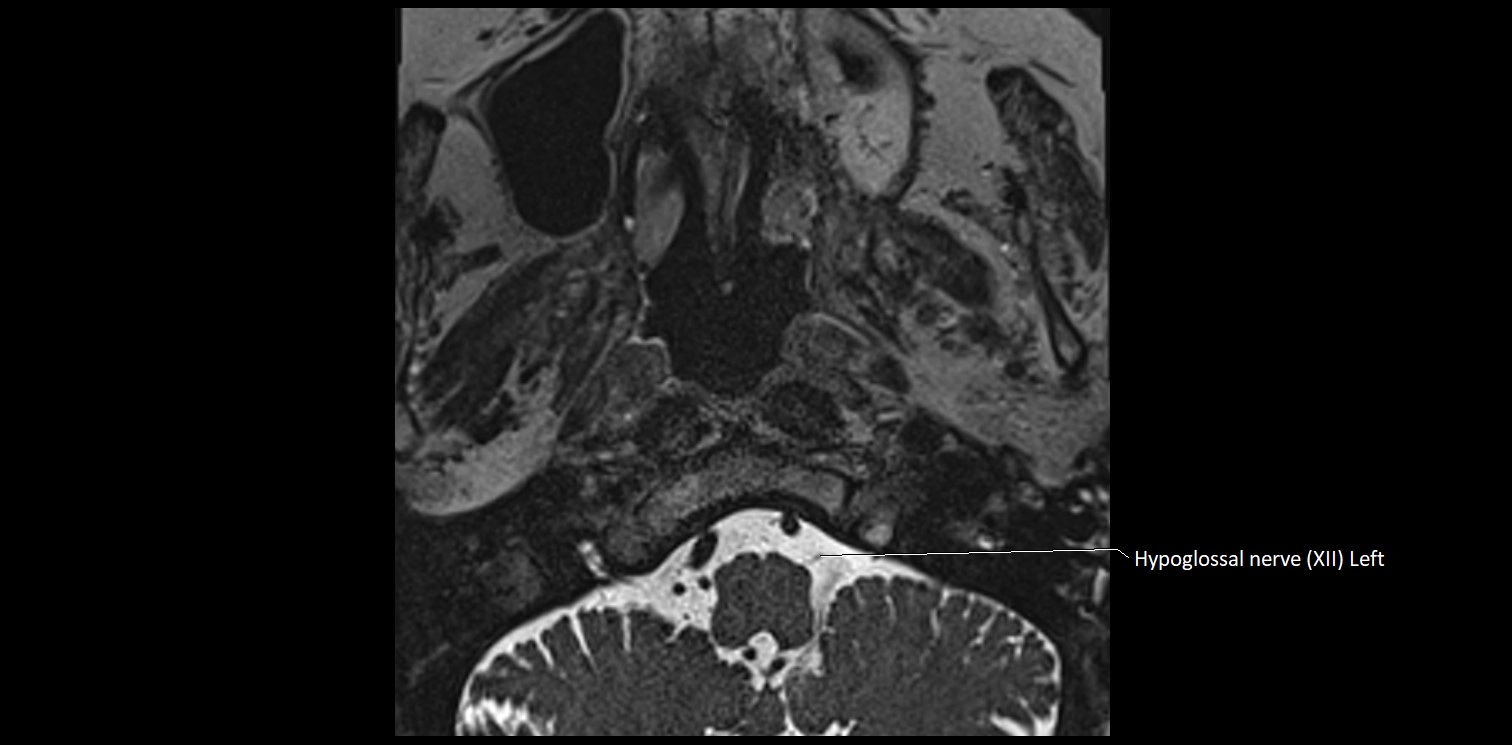

MRI images

image